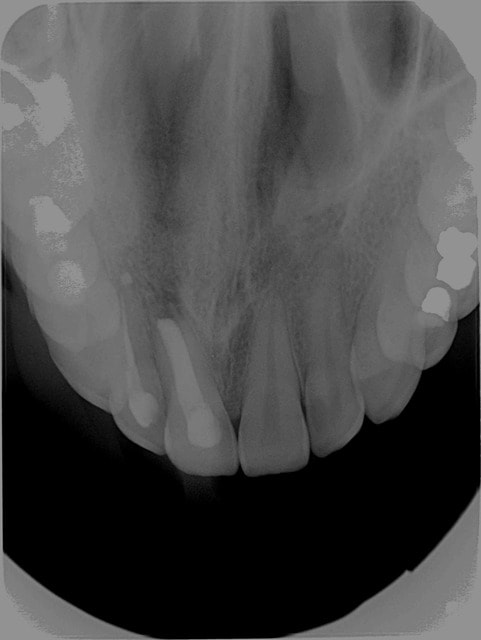

Possibilité d'avoir différentes tailles de capteurs : pour les dents antérieures voir pour des grandes rétro coronaires permettant d'avoir les DDS.

Qualité des images